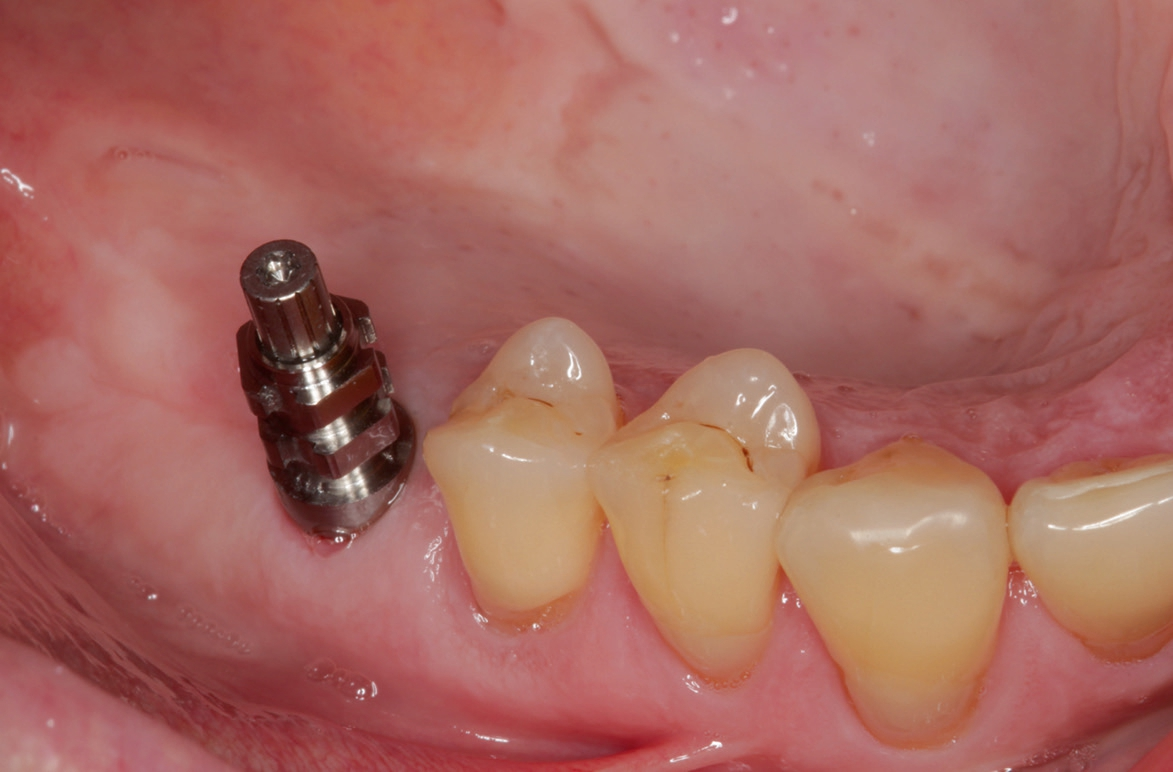

Nach lokaler Anästhesie wurden ein Kieferkammschnitt und eine nur minimale Mobilisation des Mucoperiostlappens durchgeführt. Beim internen Sinuslift nach Summers wird die Pilotbohrung bis ca. 1 mm vor die Begrenzung der Kieferhöhle vorgenommen und je nach Knochenangebot und Qualität mittels verschiedener Osteotome (Institut Straumann) weiter aufbereitet. Unabdingbar ist dabei die regelmäßige Kontrolle der Unversehrtheit der Schneider‘schen Membran durch einen „Nasenblasversuch“. Nach erfolgreicher Aufbereitung des Lagers konnte ein Implantat Größe 4,1/10 mm sehr gut primärstabil inseriert werden, anschließend primärer Wundverschluss mittels 5/0 monophiler Naht. Nach vier Monaten erfolgte die minimalinvasive Freilegung und Applikation des Gingivaformers.